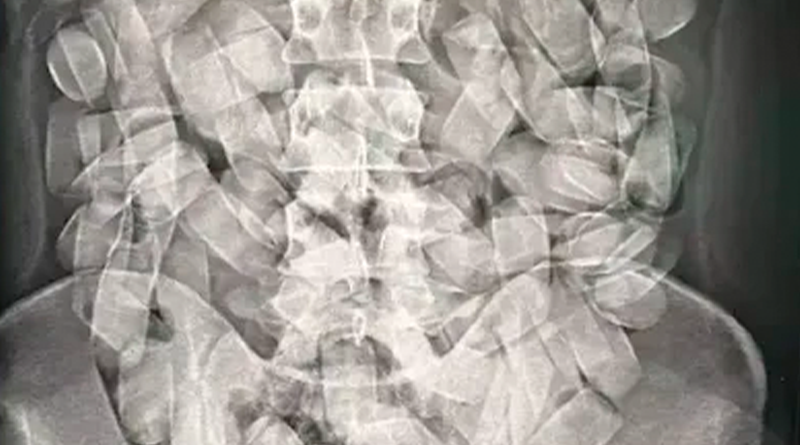

(Raio-x mostrou que passageiro ingeriu cápsulas com a droga. (Foto: Divulgação/PF)

A presença da droga no estômago do passageiro foi detectada pelo raio-x. Nesta semana, essa foi a segunda prisão em flagrante por tráfico de drogas no aeroporto de Corumbá.

A ingestão de cápsulas é uma das mais arriscada modalidades de transporte da cocaína. Pois, se alguma se romper no estômago, há risco de morte.